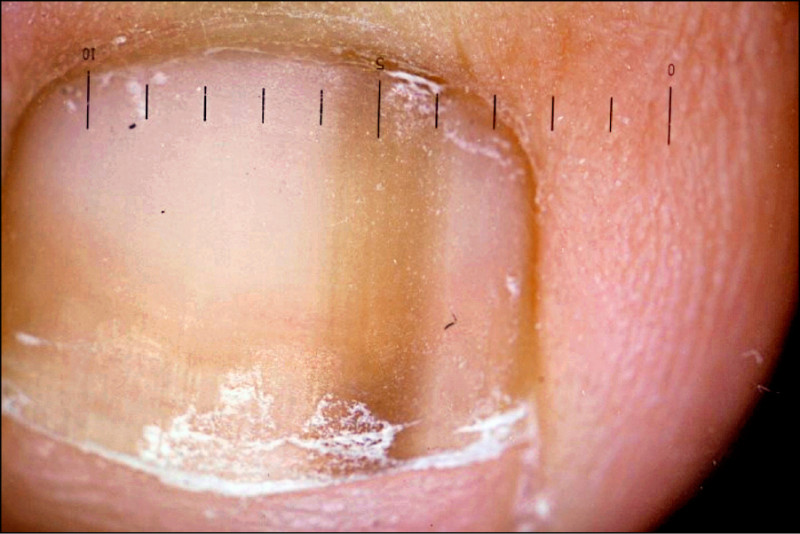

●指甲下出血(圖1):最常發生在大拇趾,主要和趾頭受到外力傷害有關,例如曾受過撞擊或在登山活動、長途健行後發生。這些血塊會隨著指甲或趾甲的生長逐漸往外移動,最後排出。若發生在腳趾甲,因趾甲生長速度較慢的緣故,耗時也會比較長,但只要有緩慢向前移動,就不需要特別擔心。